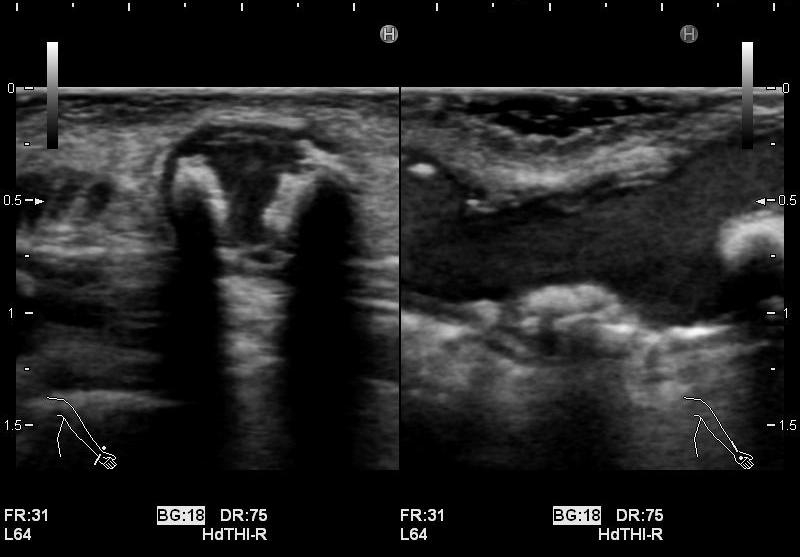

・静脈系の観察

吻合部から中枢へ向かって走査し、血管の走行や太さ、血管までの深さ、狭窄や石灰化、血栓等の有無を観察しています。長軸断面、短軸断面それぞれで観察し、また、カラードプラも使用しできるだけ正確に、血管内の状況を把握するようにしています。